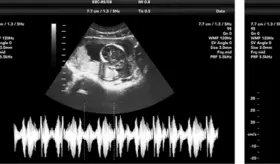

El diagnóstico de las cardiopatías ideal es durante el embarazo mediante ecografía gestacional, y si no se detecta, se realiza un tamizaje neonatal con prueba de saturación de oxígeno.